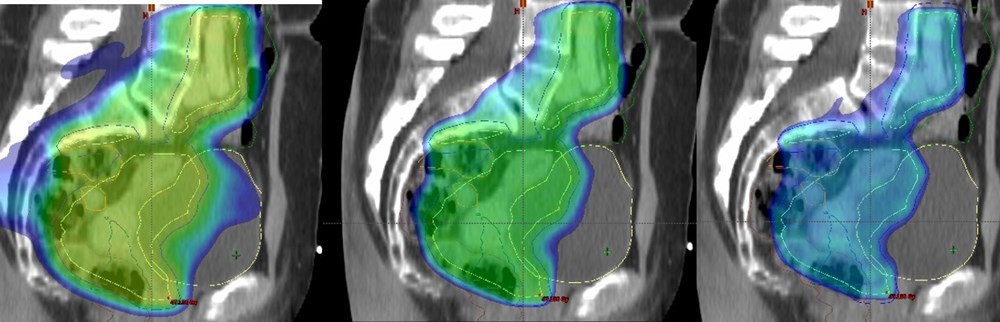

Livmoderhalskræft (IP12)

Strålebehandling udgør en væsentlig komponent i behandlingen af gynækologiske cancere og er i Danmark centraliseret på de store Universitetshospitaler for hovedparten af diagnoserne.

Med dette projekt ønsker vi overordnet at ensrette og forbedre strålebehandlingen gennem en fælles forskningsindsats. Det nationale samarbejde inkluderer samtlige behandlende hospitaler i landet. Projektet udgøres af en række delprojekter, der omfatter strålebehandling af kræft i livmoderen, livmoderhalsen, skeden, og de ydre kønsorganer.